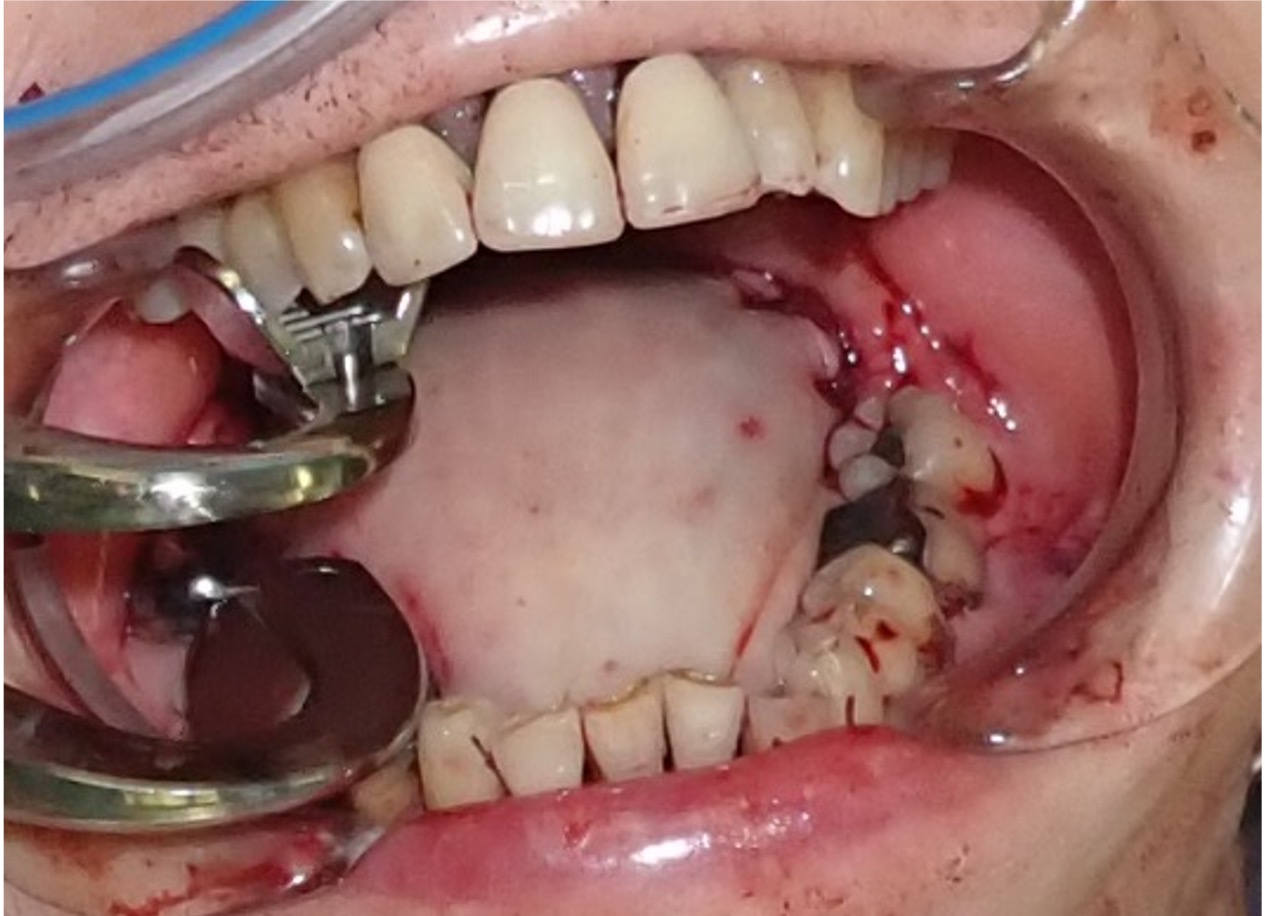

The lateral thoracic artery was identified by the descending lateral border of the pectoralis major. The lateral thoracic artery was cut at the branch of the subclavian artery and was preserved in the flap (Figure 2B). An intravenous injection of 2 mL ICG (2.5 mg/mL; Diagnogreen; Daiichi-Sankyo Pharmaceutical) was administered to the patient. Three minutes later, a staining defect was observed on the caudal side of the flap, and a supercharged PMMC flap was used (Figure 2C). The flap was moved into the oral cavity, and the lateral thoracic artery was anastomosed with the superior thyroid artery under microscopic visualization (Figure 3).

After surgery, the flap was fully adapted. No blood flow failure was noted during the 3 months of postoperative follow-up (Figure 4).